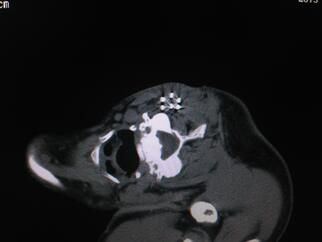

我科在省内首先开展CT引导下全身各部位经皮同轴穿刺活检术处于领先地位。已经成功完成肺、纵隔、腹盆腔、腹膜后、脊柱及四肢骨组织等部位穿刺活检 1000余例,积累一定经验。活检最小病灶约0.5厘米、活检部位深及纵隔内各组淋巴结,解决了肿瘤病理及基因诊断方面实际问题,使患者更加精准、精细化 的个体治疗手段成为可能。另外肿瘤晚期复发及转移瘤粒子植入内放疗,囊肿、脓肿及吻合口瘘穿刺引流术等,也都取得了较好的临床疗效。

同轴穿刺技术其原理是在穿刺活检取材装置外面加了一个保护装置,像圆珠笔一样,笔头贴到肿瘤表面,真正取出肿瘤组织的器械是“笔芯”——即活检枪,取材结

束后,笔芯退回到圆珠笔壳内,这个外壳就是个保护通道,无需移动,不进入瘤体内,有效避免肿瘤细胞外漏,防止肿瘤种植及针道转移,可起到最大的保护作用。

笔芯可多次自由进出针壳,多次、多点取材,取材量大,完全能保证病理及基因诊断。其适应症广,相对禁忌症及绝对禁忌症少;只要是无全身严重心、脑及肺疾

病,能耐受相对久卧、静止体位,短时间屏气,常规检查无异常者均可实施。同轴穿刺活检技术可有效减少气胸、出血等常见并发症。

微创不等于无创,还是存在一定风险;我们经过临床工作总结一些经验、自创一些实用新的方法:对于年纪大配合不理想、肺部有严重肺气肿及肺大泡者、病灶小、 位置深及特殊部位者,通过术前与患者本人及家属沟通,使其能充分配合。采取一人扫描定位一人穿刺进针的二人操作方法;设计最合理进针路线。在胸腔外准确定 位,争取最少次数通过胸膜。通过注水扩大组织间隙及独创“针水同行”方法避免损伤胸壁及肺内针道周围血管等方法及措施,使以前不可能实现的活检变为可能。